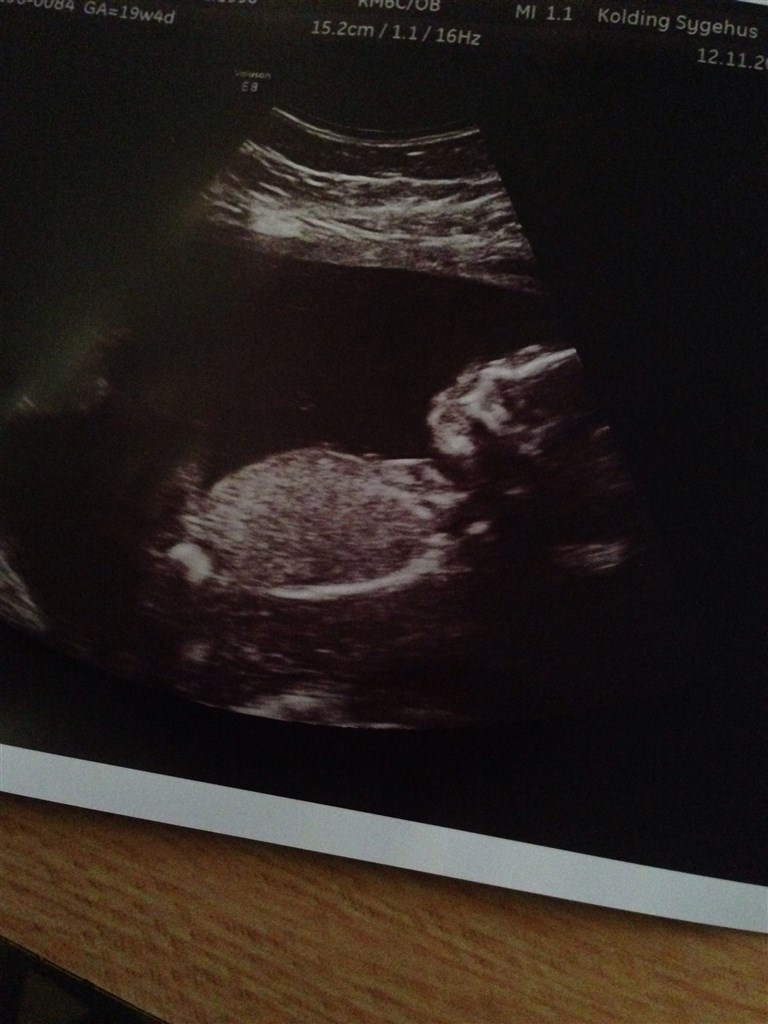

Ved ik om de her billeder kan bruges.

Vedhæftede fotos (klik for at se i fuld størrelse)